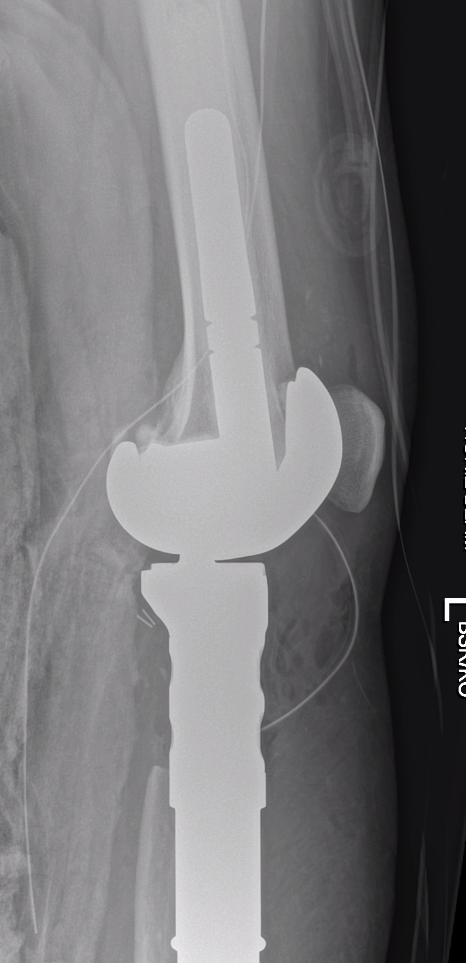

Management

Wide Resection

A. Hemicortical resection and posterior hemicortical allograft reconstruction

- no chemotherapy if low grade

- hemicortical resection and hemicortical allograft reconstruction

- 22 cases (6 parosteal, 6 peripheral chondrosarcoma, 10 adamantinoma)

- all allografts incorporated

- 6/22 (27%) patients had a fracture of the remaining host hemicortex

- good excellent functional outcome in 21/22 patients

- 111 cases (18 parosteal, 37 adamantinoma)

- 18% host bone fracture

- 7% nonunion

- 7% infection

- 3% allograft fracture